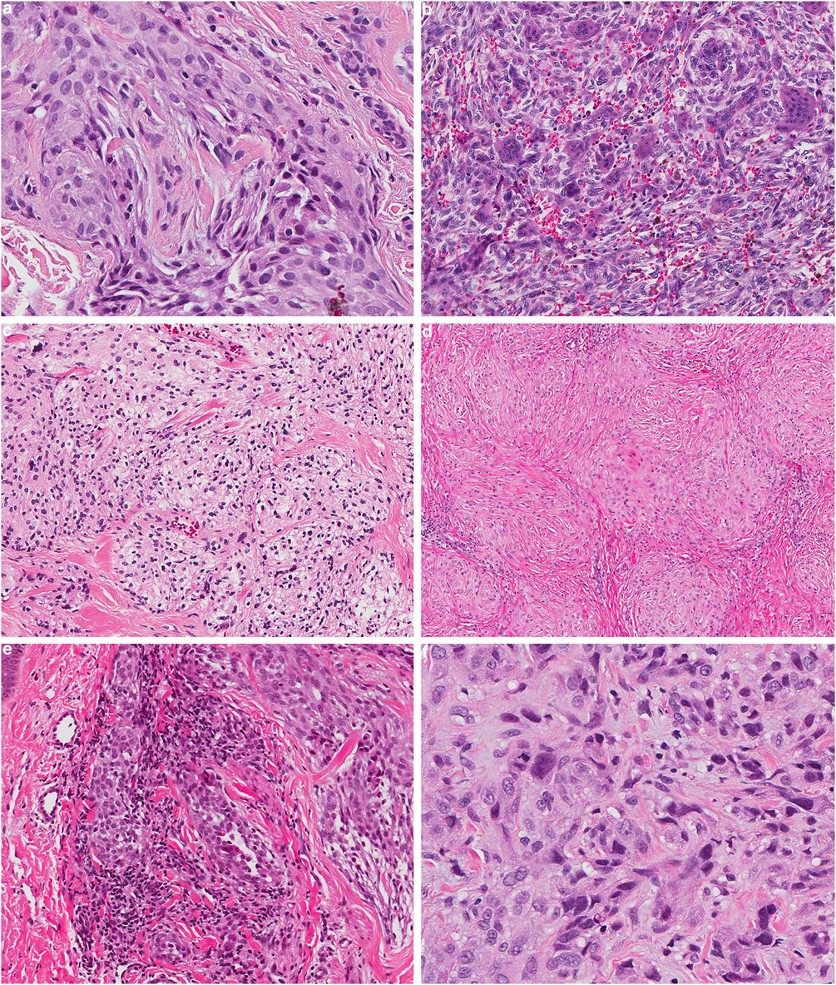

Xanthogranulomatous epithelial tumor: report of 6 cases of a novel, potentially deceptive lesion with a predilection for young women | Modern Pathology

image size: 1843x1382

Xanthogranulomatous epithelial tumors and keratin-positive giant cell-rich soft tissue tumors: two aspects of a single entity with frequent HMGA2-NCOR2 fusions - Modern Pathology

image size: 2001x1409